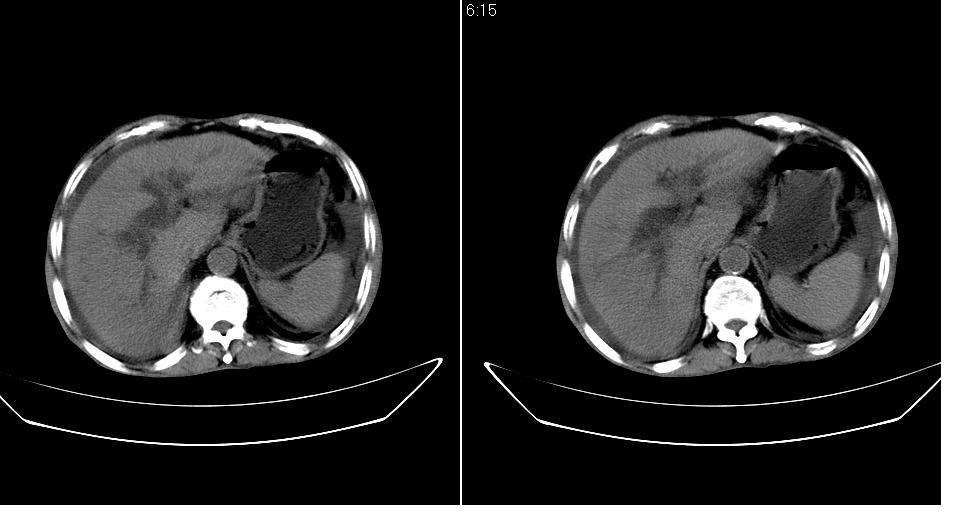

男 78岁,全身黄染,病人家属拒绝增强。

肝周 脾周 胆囊窝内明显积液,胆囊扩大,胆囊壁模糊,肝内胆管扩张。考虑;胆囊癌周边侵润伴腹水。

周 脾周 胆囊窝内明显积液,胆囊扩大,胆囊壁模糊,肝内胆管扩张。考虑;胆囊癌周边侵润伴腹水。

支持胆囊癌周边侵润伴腹水。

考虑;胆囊癌周边侵润伴腹水。